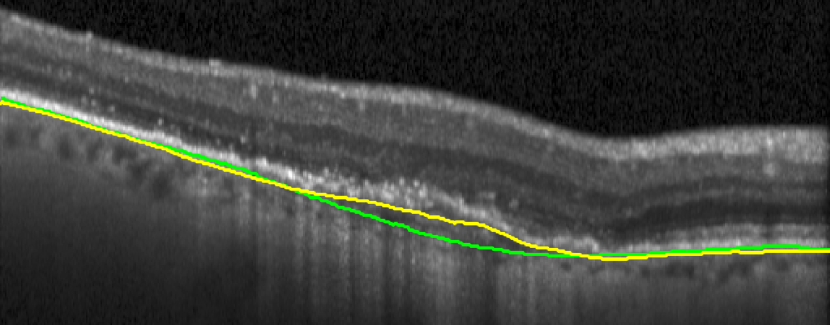

A representative example of the influence of the curvature term is shown in Fig. 17. The proposed method with the help of the curvature term correctly finds the BM as opposed to Proposed w/o w/o TPS. The associated uncertainty is also adequately higher, signaling the lower confidence of the BM position estimate in this region. In contrast, the absence of leads to a poor uncertainty estimation in some incorrect segmentation regions.

(a)

(b)